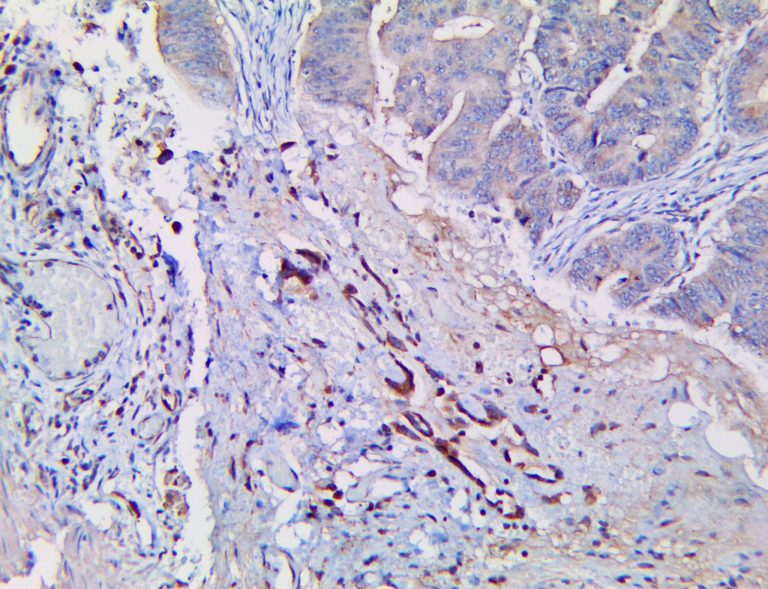

The vast majority of patients with COVID-19 have had a good prognosis, but there are still some critical individuals and even death.10 Most of these critically ill and dead patients do not develop severe clinical manifestations in the early stages of the disease. Some patients only show mild fever, cough, or muscle soreness. These conditions suddenly deteriorate in the later stages of the disease or in the recovery process . Acute respiratory distress syndrome (ARDS) and multiple-organ failure occur rapidly, resulting in death within a short time. Cytokine storm is considered to be one of the major causes of ARDS and multiple organ failure.

Cytokine Storm Syndrome (CSS) is characterized by systemic symptoms and signs derived from a massive and uncontrolled inflammatory response caused by pro- and anti-inflammatory cytokine dysregulation. Viruses, such as Herpes and Epstein-Barr are known to trigger CSS, as is H5N1 influenza. Current literature indicates that SARS-CoV-2 triggers CSS and has been attributed to the severe symptoms’ characteristic of critical patients. CSS in these patients is often fatal, as was the case in the previous SARS and MERS outbreaks.